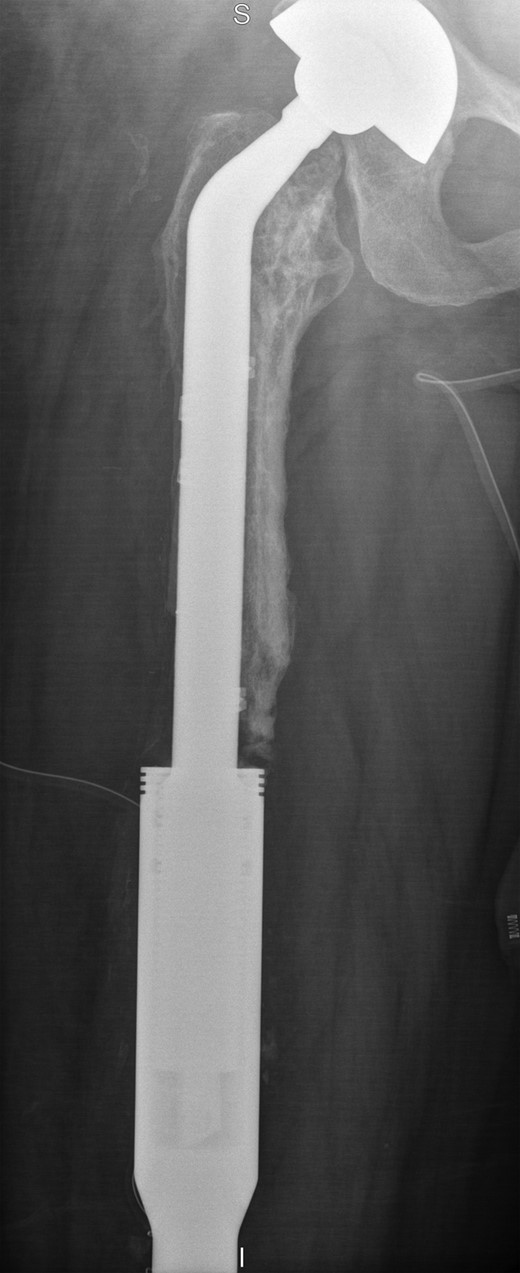

She remained well for 5 years, until she was referred back to our joint reconstruction unit due to a stress fracture in the stem of the distal femoral component, just below the junction with the cement-linked internal proximal femoral replacement (Fig. 5).

Full length femur radiograph illustrating fatigue fracture in stem of original distal femoral component.